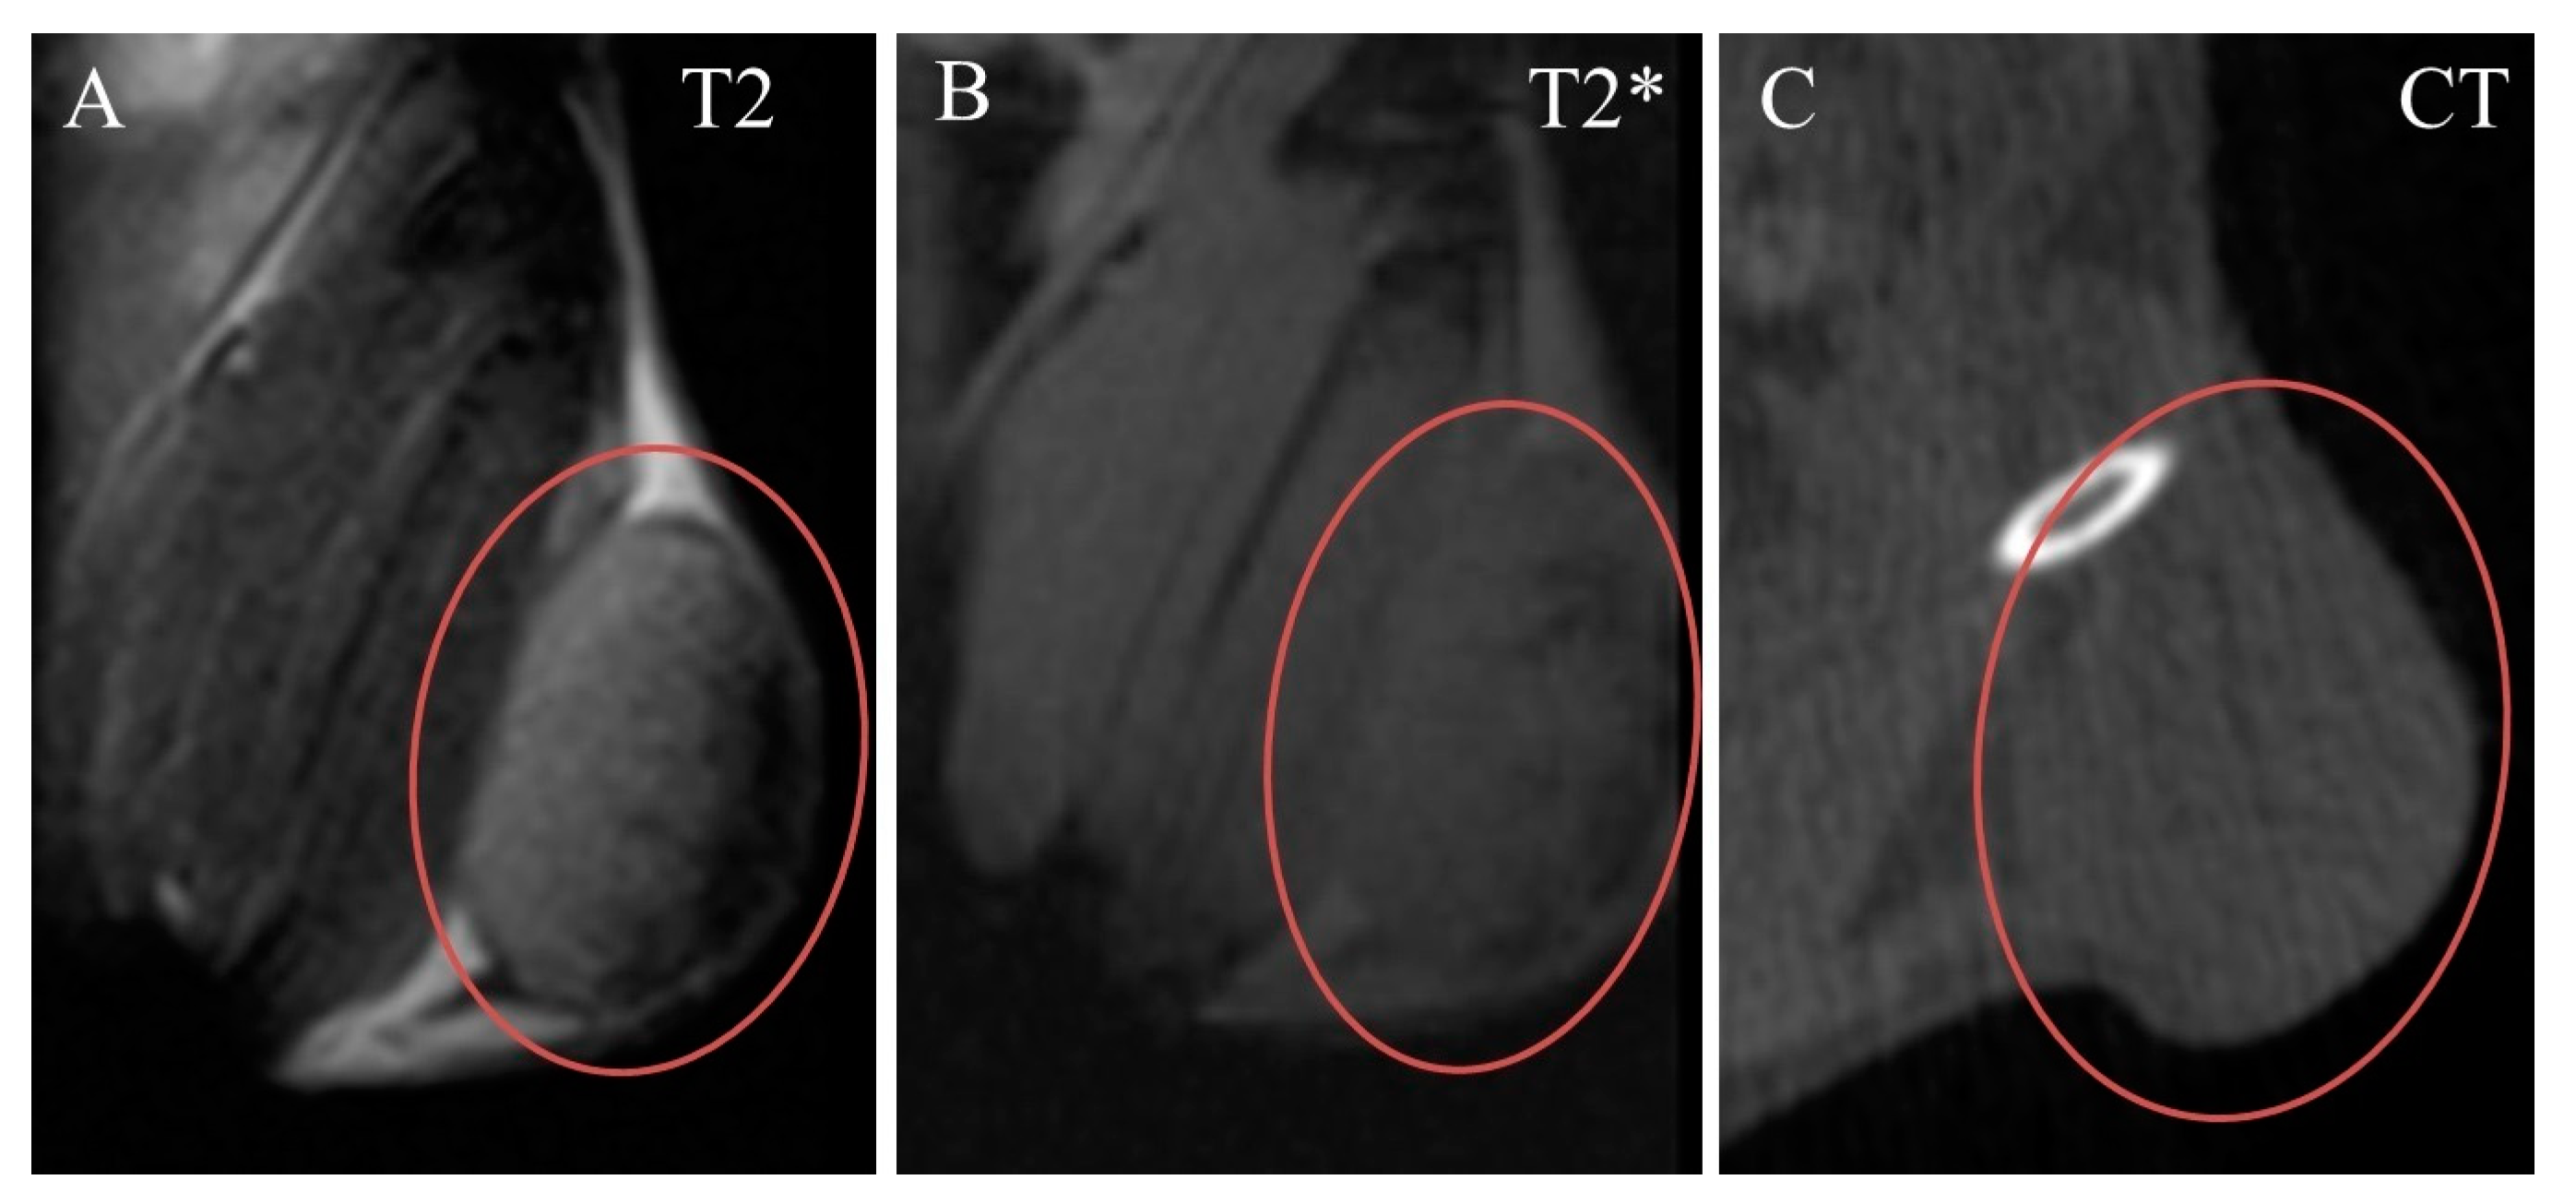

2. Results